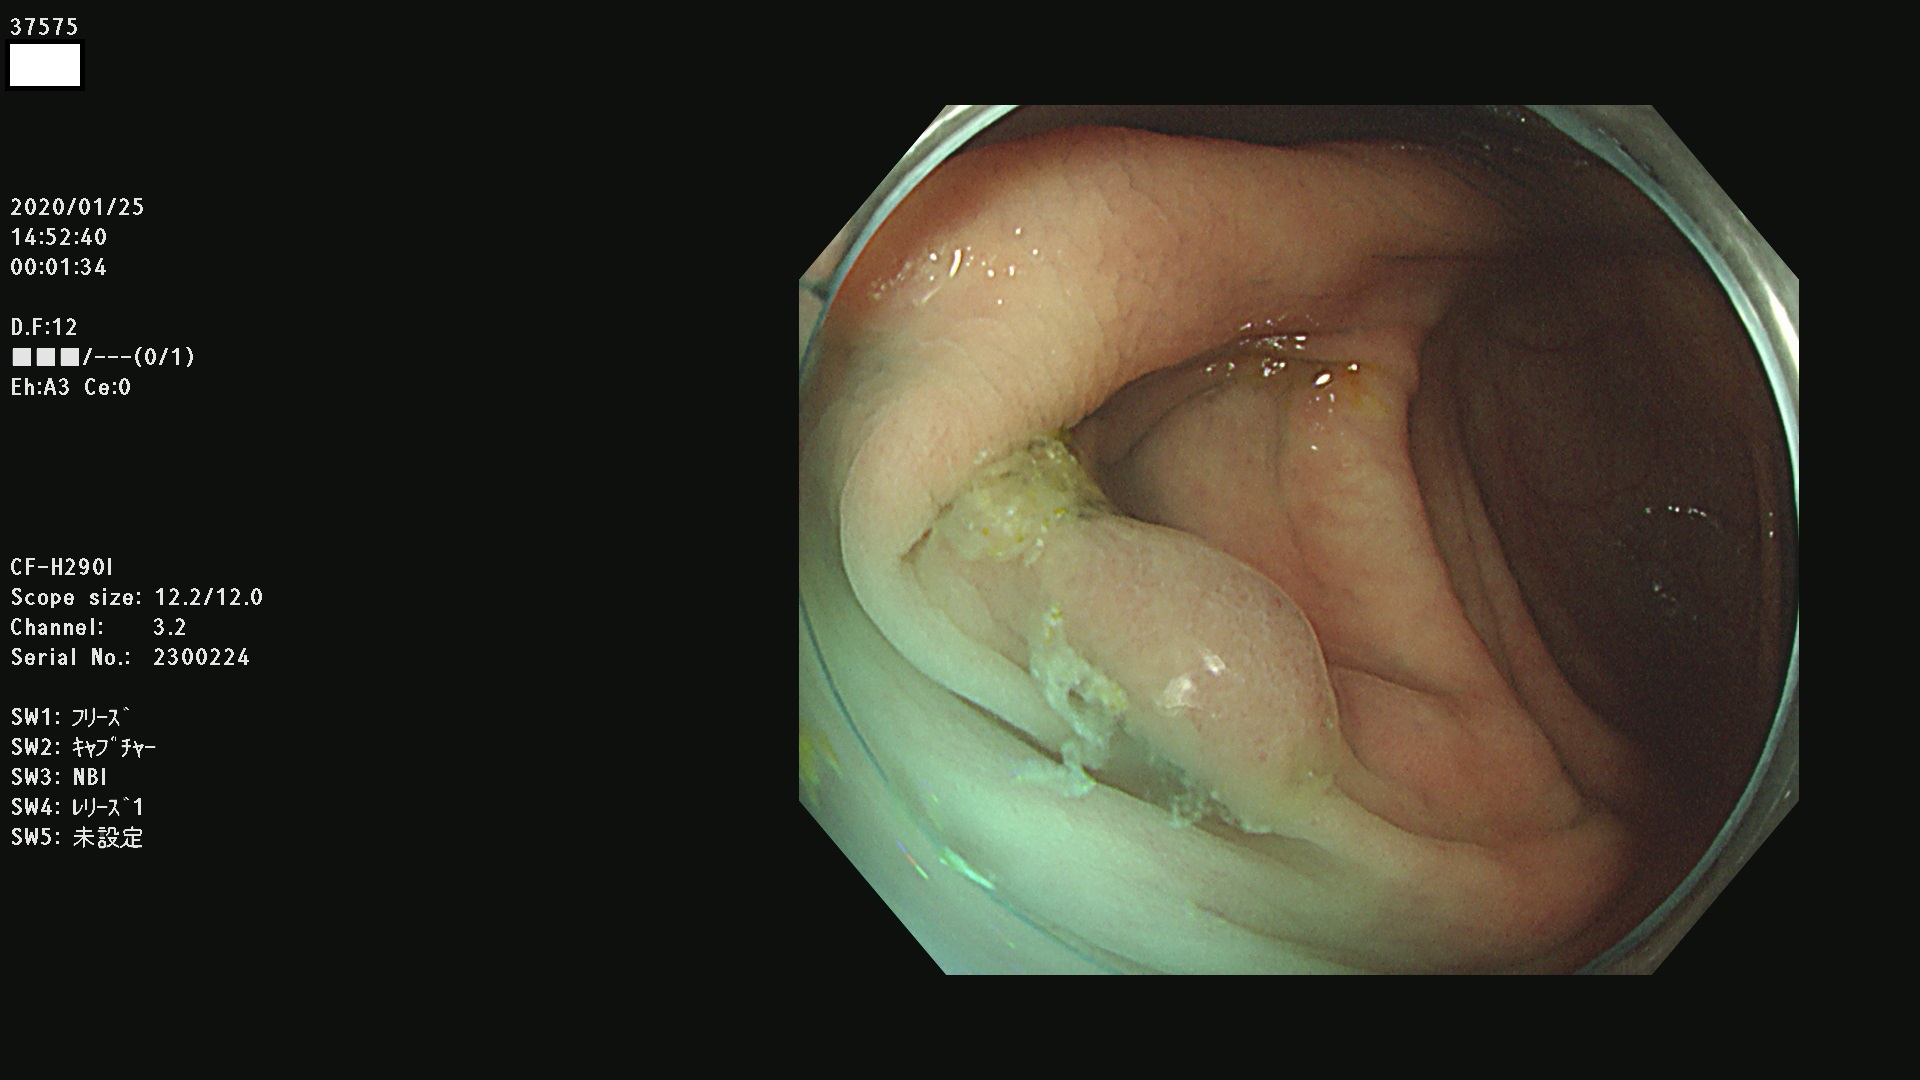

腺腫発見率 67 % (カルテ番号 37500〜37599の100名の方の検査結果で集計)大腸癌検診最新情報

以下のカルテ番号の方に腺腫(Adenoma,Group3〜5)が見つかりました(集計法)

37500 37502 37503 37505 37508 37509 37510 37511 37512 37513 37514 37517 37519 37520 37521 37525 37526(SSAPのみ) 37527 37528 37529 37531 37532 37533 37534 37536 37538(SSAPのみ) 37539 37541 37542 37543 37547 37548 37549(SSAPのみ) 37550 37552 37555 37556 37561 37562 37563(SSAPのみ) 37564 37565 37566 37567 37568 37570 37571 37572 37573 37574 37575(SSAPのみ) 37576 37577 37579 37580 37582 37583 37586(SSAPのみ) 37587 37588(SSAPのみ) 37590 37593(SSAPのみ) 37594 37596 37597(SSAPのみ) 37598 37599

発見困難で危険性の高い平坦型病変(上記100名より抽出) ![]()